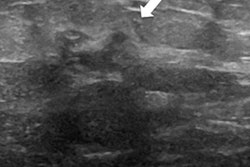

The national breast screening program in England gives clear guidance on breast health and assessment that's based on standard triple assessment and includes further mammographic views where applied and digital breast tomosynthesis (DBT) when available. Targeted ultrasound of suspicious lesions with a needle biopsy is employed where appropriate. The guidelines also mention extending the ultrasound examination to include the whole ipsilateral breast if the breasts are dense, but this isn't mandatory at the moment, Scott said.

Previous data published by researchers from St. George's has shown bilateral whole-breast ultrasound increases the preoperative diagnosis of multiple tumors, so all women with a suspicious solid lesion on ultrasound receive this treatment at their hospital.

Using the local protocol to scan the whole ipsilateral breast, the researchers identified 3% more cancers than the standard protocol alone, which was statistically significant. Scanning the whole contralateral breast, they identified 1% more cancers than the standard protocol alone, which was not statistically significant.

"As expected, we found there was still a significant pickup rate of additional cancers using ultrasound, particularly in the ipsilateral breast, but this was less dramatic than our previously published data, possibly secondary to the introduction of the newer mammography techniques," Scott noted.

Few studies in the literature comment on ipsilateral whole-breast ultrasound. One small study showed a 10% additional pickup rate of ultrasound over mammogram alone when scanning the whole ipsilateral breast in a mixed screening/symptomatic setting. The findings at St. George's with a purely screening population were smaller but still significant, she added.